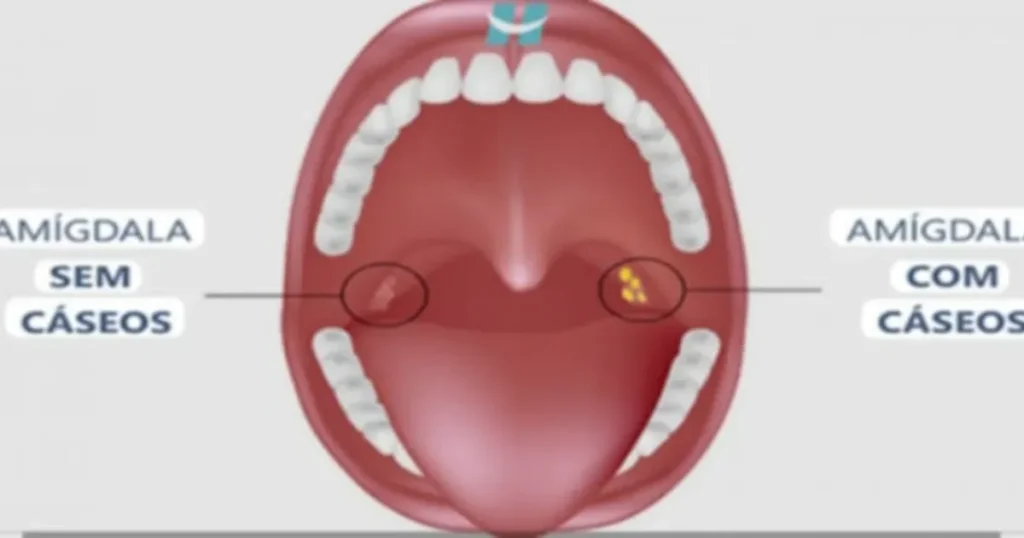

Essas pequenas formações aparecem nas amígdalas e geralmente têm coloração branca ou amarelada, além de um cheiro forte e desagradável. Muitas pessoas só percebem sua existência quando sentem o gosto ruim na boca ou quando eliminam essas bolinhas ao tossir, espirrar ou até falar.

A formação dos cáseos está diretamente ligada à estrutura das amígdalas. Elas possuem pequenas cavidades naturais chamadas criptas, onde resíduos podem se acumular.

Dentro dessas cavidades, ocorre o acúmulo de diferentes substâncias, como restos de alimentos, células mortas, muco e bactérias. Com o tempo, esse material fica preso e começa a se decompor, formando pequenas massas endurecidas.

Esse processo de decomposição é o principal responsável pelo odor forte característico das bolinhas. As bactérias presentes produzem compostos com cheiro desagradável, o que também contribui para o mau hálito.